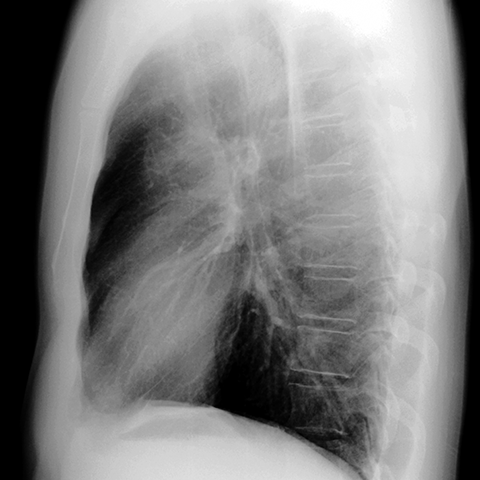

Normal anatomy of the aorta (CXR) [2 of 5]